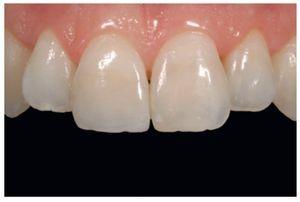

La odontología adhesiva ha permitido restaurar la funcionalidad completa de los dientes, creando una unión a los tejidos duros y conservando al mismo tiempo en la medida de lo posible los tejidos dentarios sanos (figuras. 1-3).

Figura 1 Paciente de 16 años de edad con una restauración deficiente en el diente número 11 y una erupción pasiva evidente.